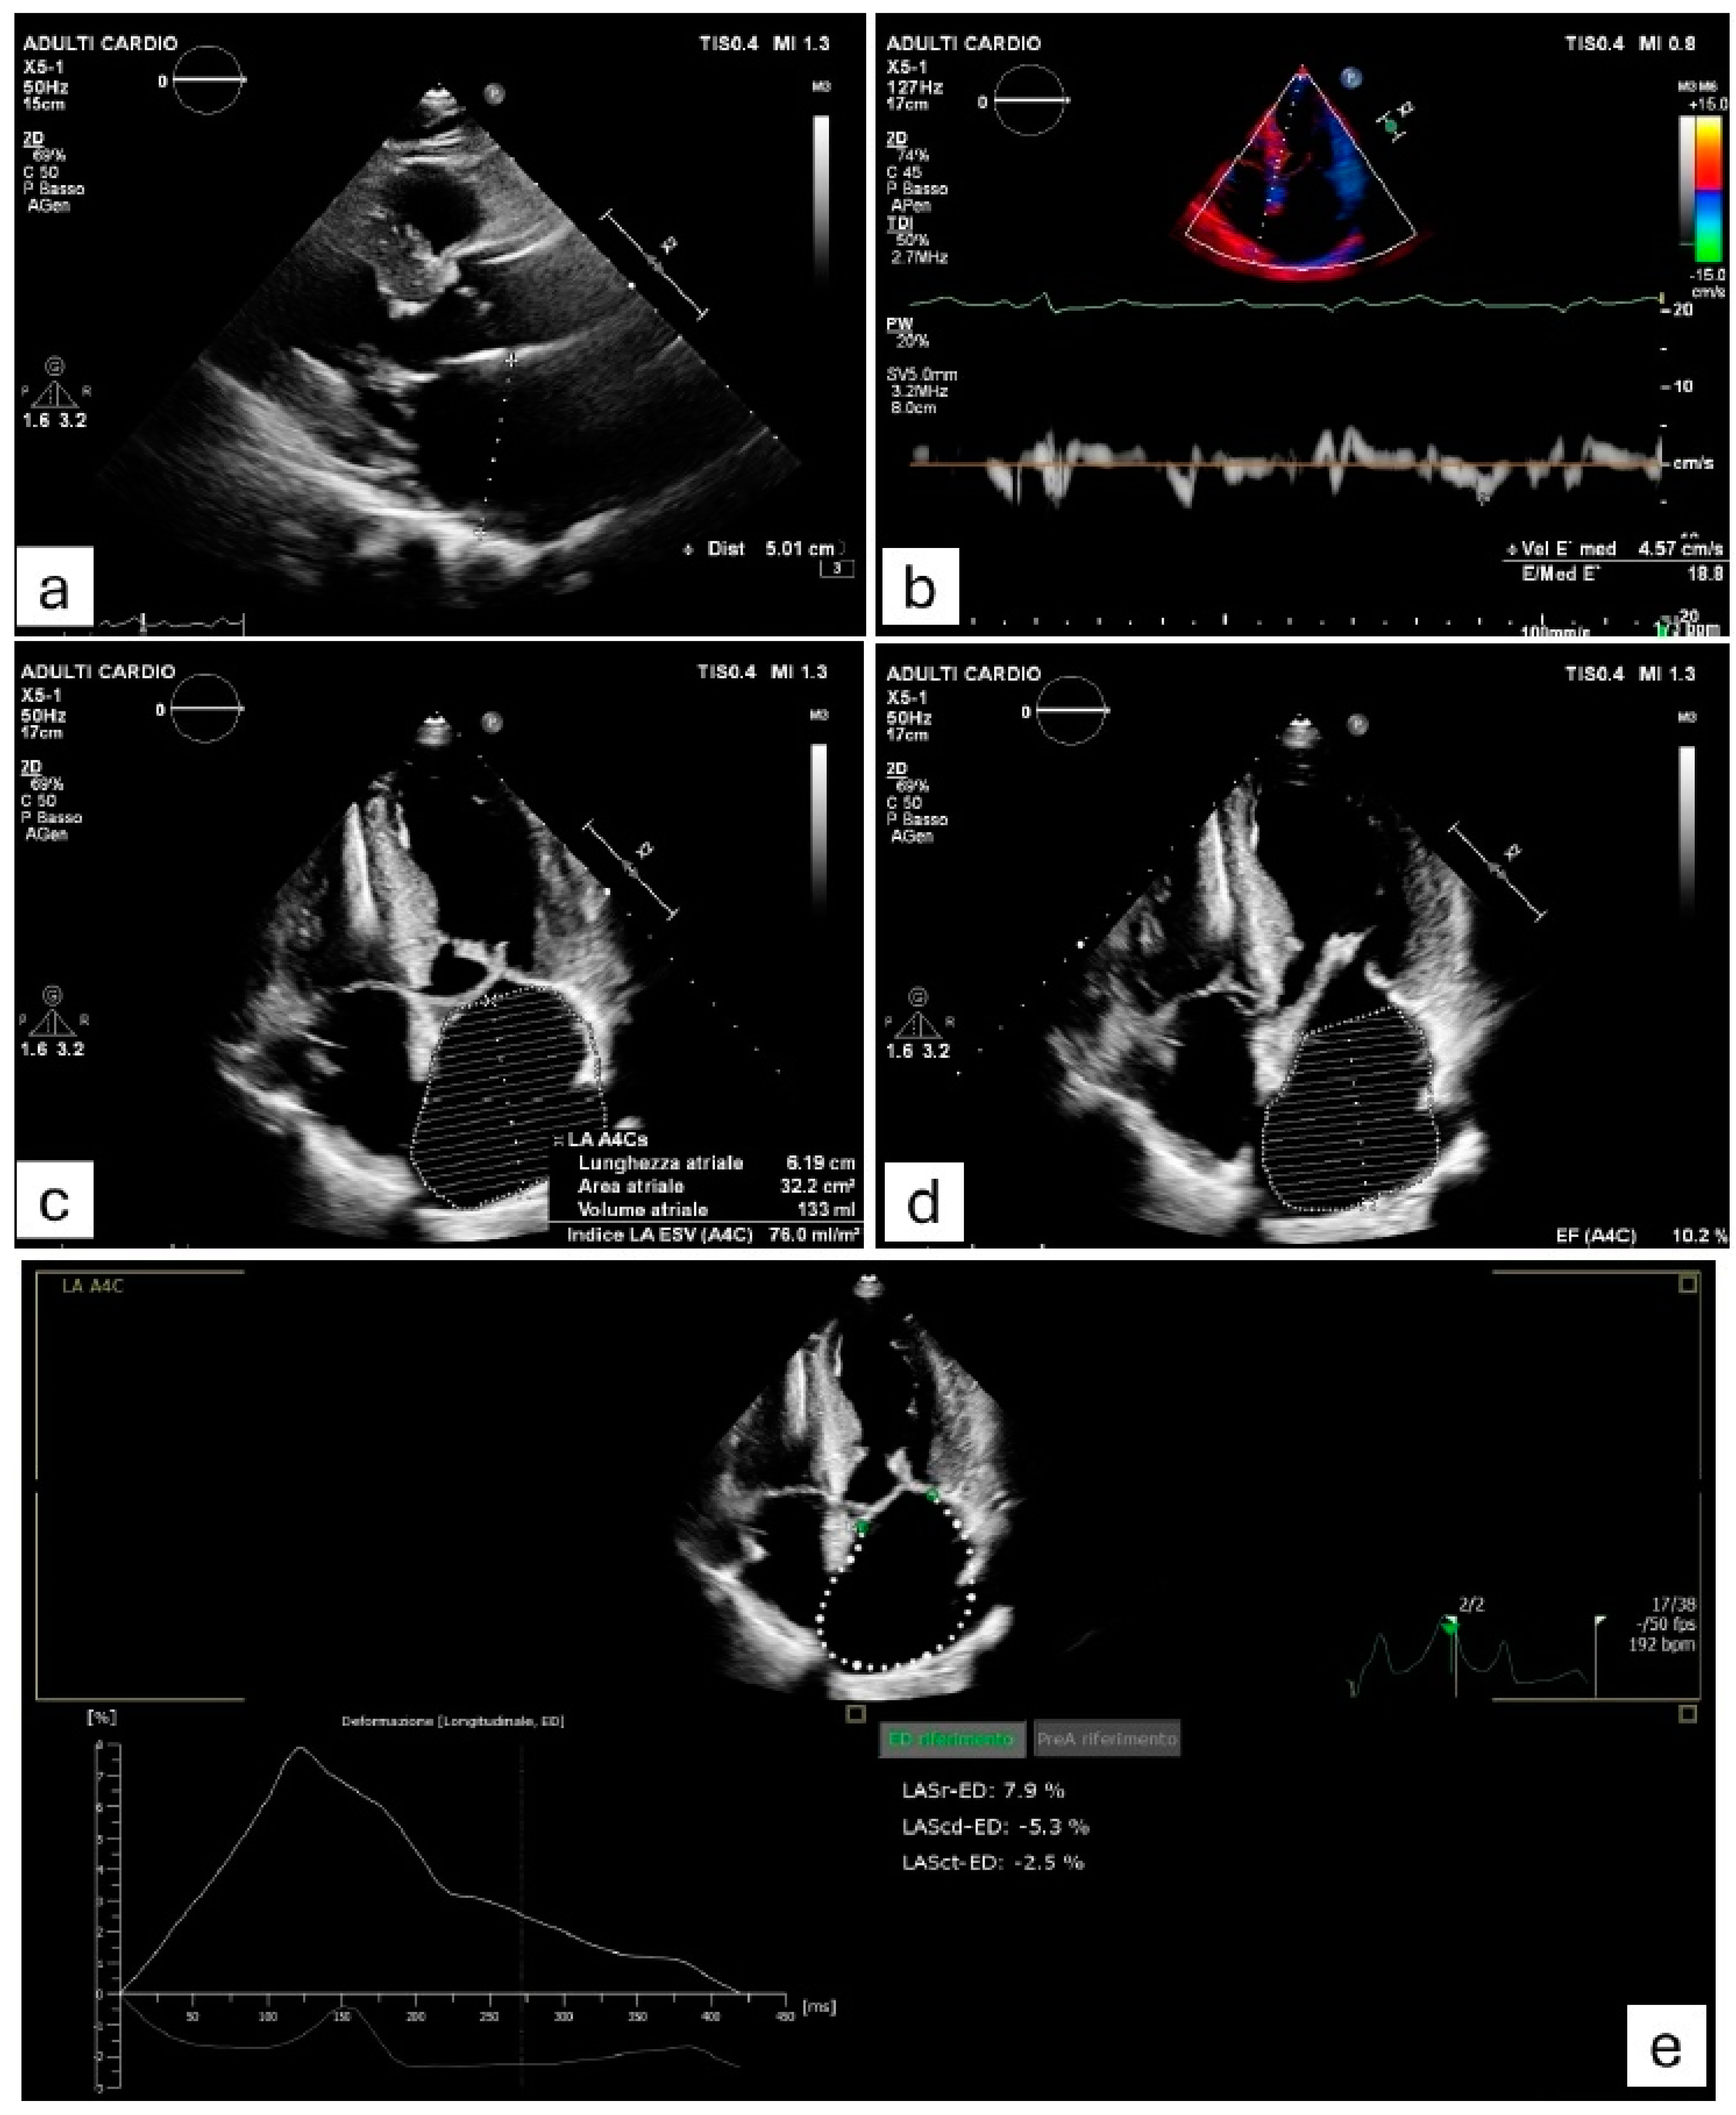

5. Structural and Mechanical Left Atrial Remodeling Detected by Imaging Techniques

| Tjahiadi et al. [22] | 2021 | 208 | Retrospective | ECG-Echo | PA-TDI LA diameter LAVI LA reservoir strain | >115 ms ≥45 mm ≥34 mL/m2 <21.3% |

| Raman et al. [78] | 2021 | 258 | Retrospective | CMR | LA booster strain LA reservoir strain Age LAEF | ≤8% ≤18% ≥55 years ≤45% |

| Parisi et al. [79] | 2024 | 141 | Prospective | Echo-CMR | LACI LAEF | >44% <43% |